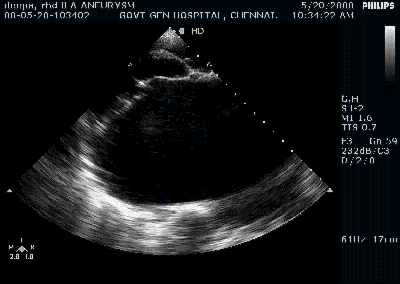

- Small verrucous vegetations (See Image )